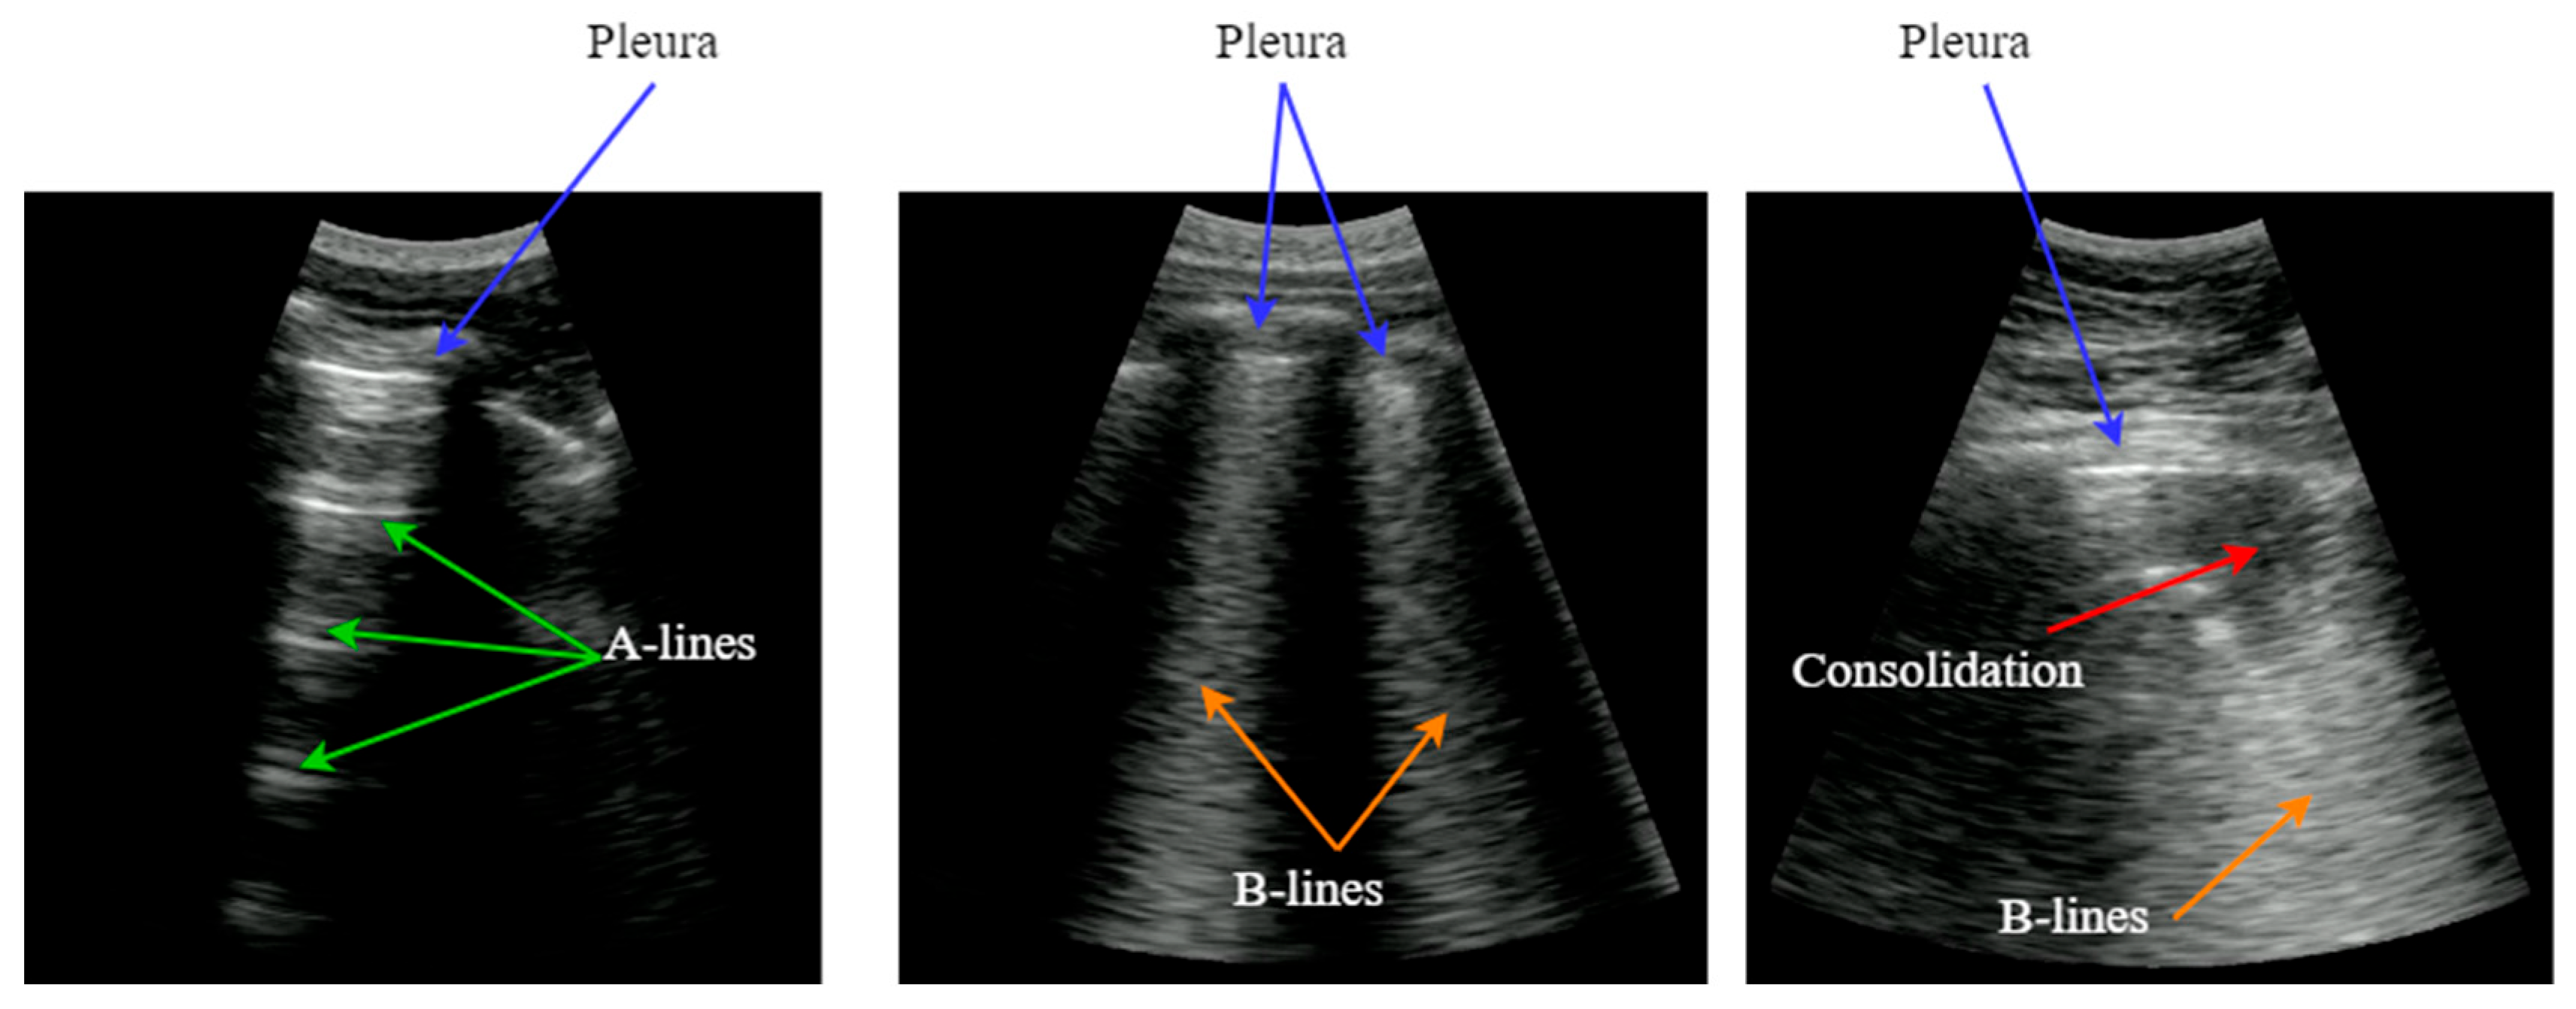

In the presence of pneumonia and other interstitial syndrome diseases, the air inside the alveoli is progressively substituted by liquid, which modifies the acoustic impedance of the lung parenchyma, making it more similar to the impedance of muscle and fat above the pleura. As the acoustic impedance difference between both tissues reduces, more energy of the incident wave passes through the pleura to the lung parenchyma. But if air remains in some alveoli, a local reverberation phenomenon occurs (acoustic trap), and a bright vertical line appears in the image because of the multiple echoes backscattered inside the lesion [3]. This vertical artifact is named B-Line, and it is indicative of the presence of pneumonia. Figure 1 shows some examples to better understand the morphology of the artifacts explained.

Figure 1.

Typical LUS artifacts: Pleura (blue), A-lines (green), B-lines (orange), Consolidation (red).

As the disease advances, more air is substituted by liquid and then consolidates into solid material. These consolidations appear in the image as hypoechoic regions and constitute the third artifact usually looked for when imaging the lung. In sum, artifacts like A-lines, B-lines, and consolidations are indicative of lung condition and can be used to diagnose a pulmonary pathology [4]. Detecting and interpreting these artifacts is the key for a correct evaluation of lung images, which has been the principal bottleneck in the dissemination of this technique.